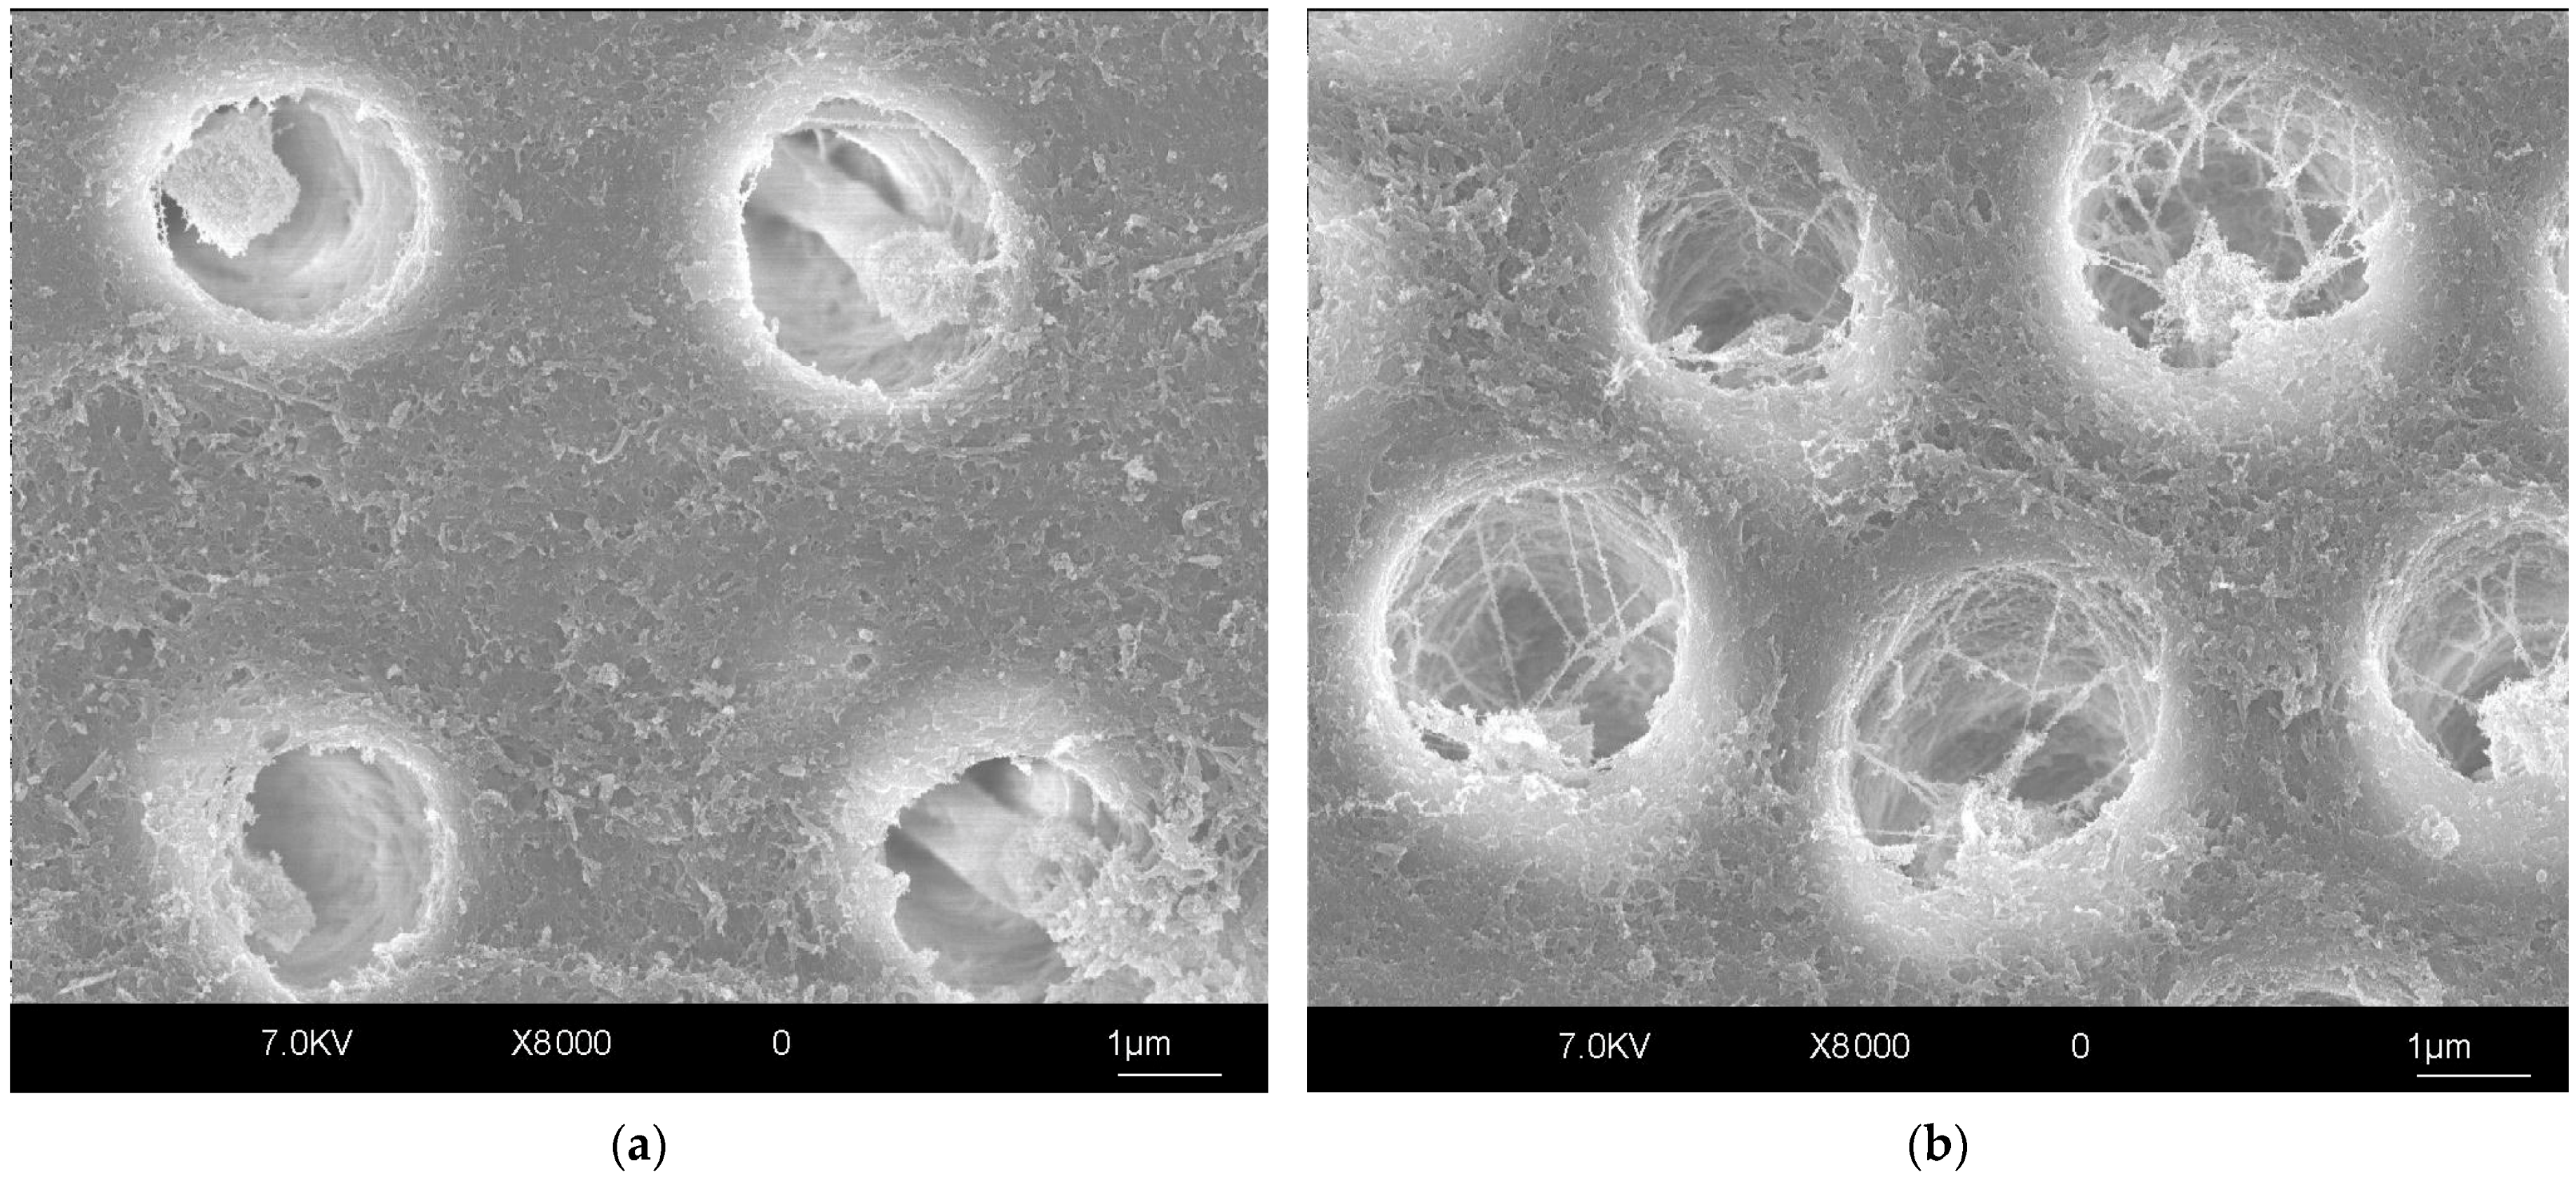

- Comba, A.; Baldi, A.; Garavelli, M.; Maravic, T.; Breschi, L.; Mazzoni, A.; Mazzitelli, C.; Scotti, N. Effects of surface pretreatments on bond strength and morphology of aprismatic enamel. J. Adhes. Dent. 2022, 24, 367–374. [Google Scholar]

- Serafino, C.; Gallina, G.; Cumbo, E.; Ferrari, M. Surface Debris of Canal Walls after Post Space Preparation in Endodontically Treated Teeth: A Scanning Electron Microscopic Study. Oral Surg. Oral Med. Oral Pathol. Oral Radiol. Endod. 2004, 97, 381–387. [Google Scholar] [CrossRef]

- Serafino, C.; Gallina, G.; Cumbo, E.; Monticelli, F.; Goracci, C.; Ferrari, M. Ultrasound Effects after Post Space Preparation: An SEM Study. J. Endod. 2006, 32, 549–552. [Google Scholar] [CrossRef] [PubMed]